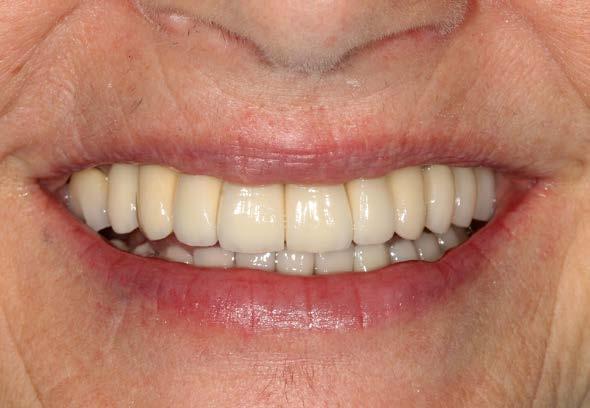

Figura 7 y 8. Fotografías de la prótesis de carga inmediata. En ellas observamos ambas prótesis (superior e inferior) colocadas horas después de la cirugía.

190. Junio 2024 17

Figuras 10 y 11. Caso finalizado 6 meses después, con las prótesis definitivas colocadas.

190.

2024 19

Junio